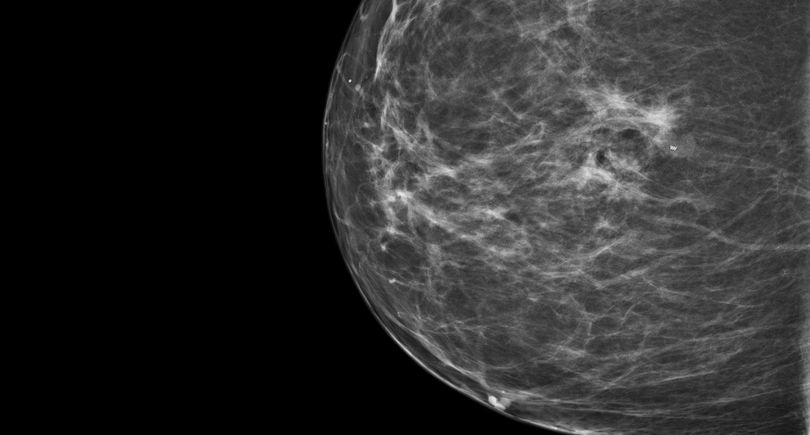

CESM is an advanced form of mammography that uses a safe dye injected into the bloodstream. This dye highlights areas of concern within the breast, giving clinicians a much clearer and more detailed image than a traditional mammogram.

“Sometimes it can be difficult to interpret a mammogram, especially in patients with dense breast tissue”, Nicole explains. “It’s a bit like looking for a cloud in a sky full of clouds. The contrast helps remove that ‘noise’ and shows us exactly what’s going on inside the breast.”

One of the biggest advantages of CESM is that it can be carried out during the patient’s breast clinic appointment and reviewed by a radiologist straight away. Before CESM was introduced, patients with unclear mammogram results often faced a longer wait for further tests, such as an MRI scan, to gather more information.